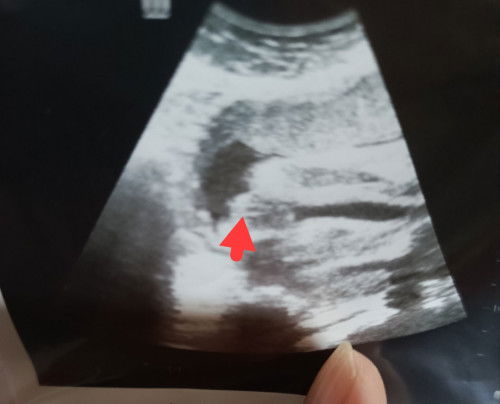

Tumpang tanya mommy2, kalau scan macam ni ada harapan ke dapat girl?

Scan jantina baby

bukan lg ada harapan sis. tp mmg girl ne haha. nmpk belahan burger nya dsituu

saya 31w scan pgi ni . mcm ni juga bentuk nya.. hehehe

yang tu sis

mcm garis2